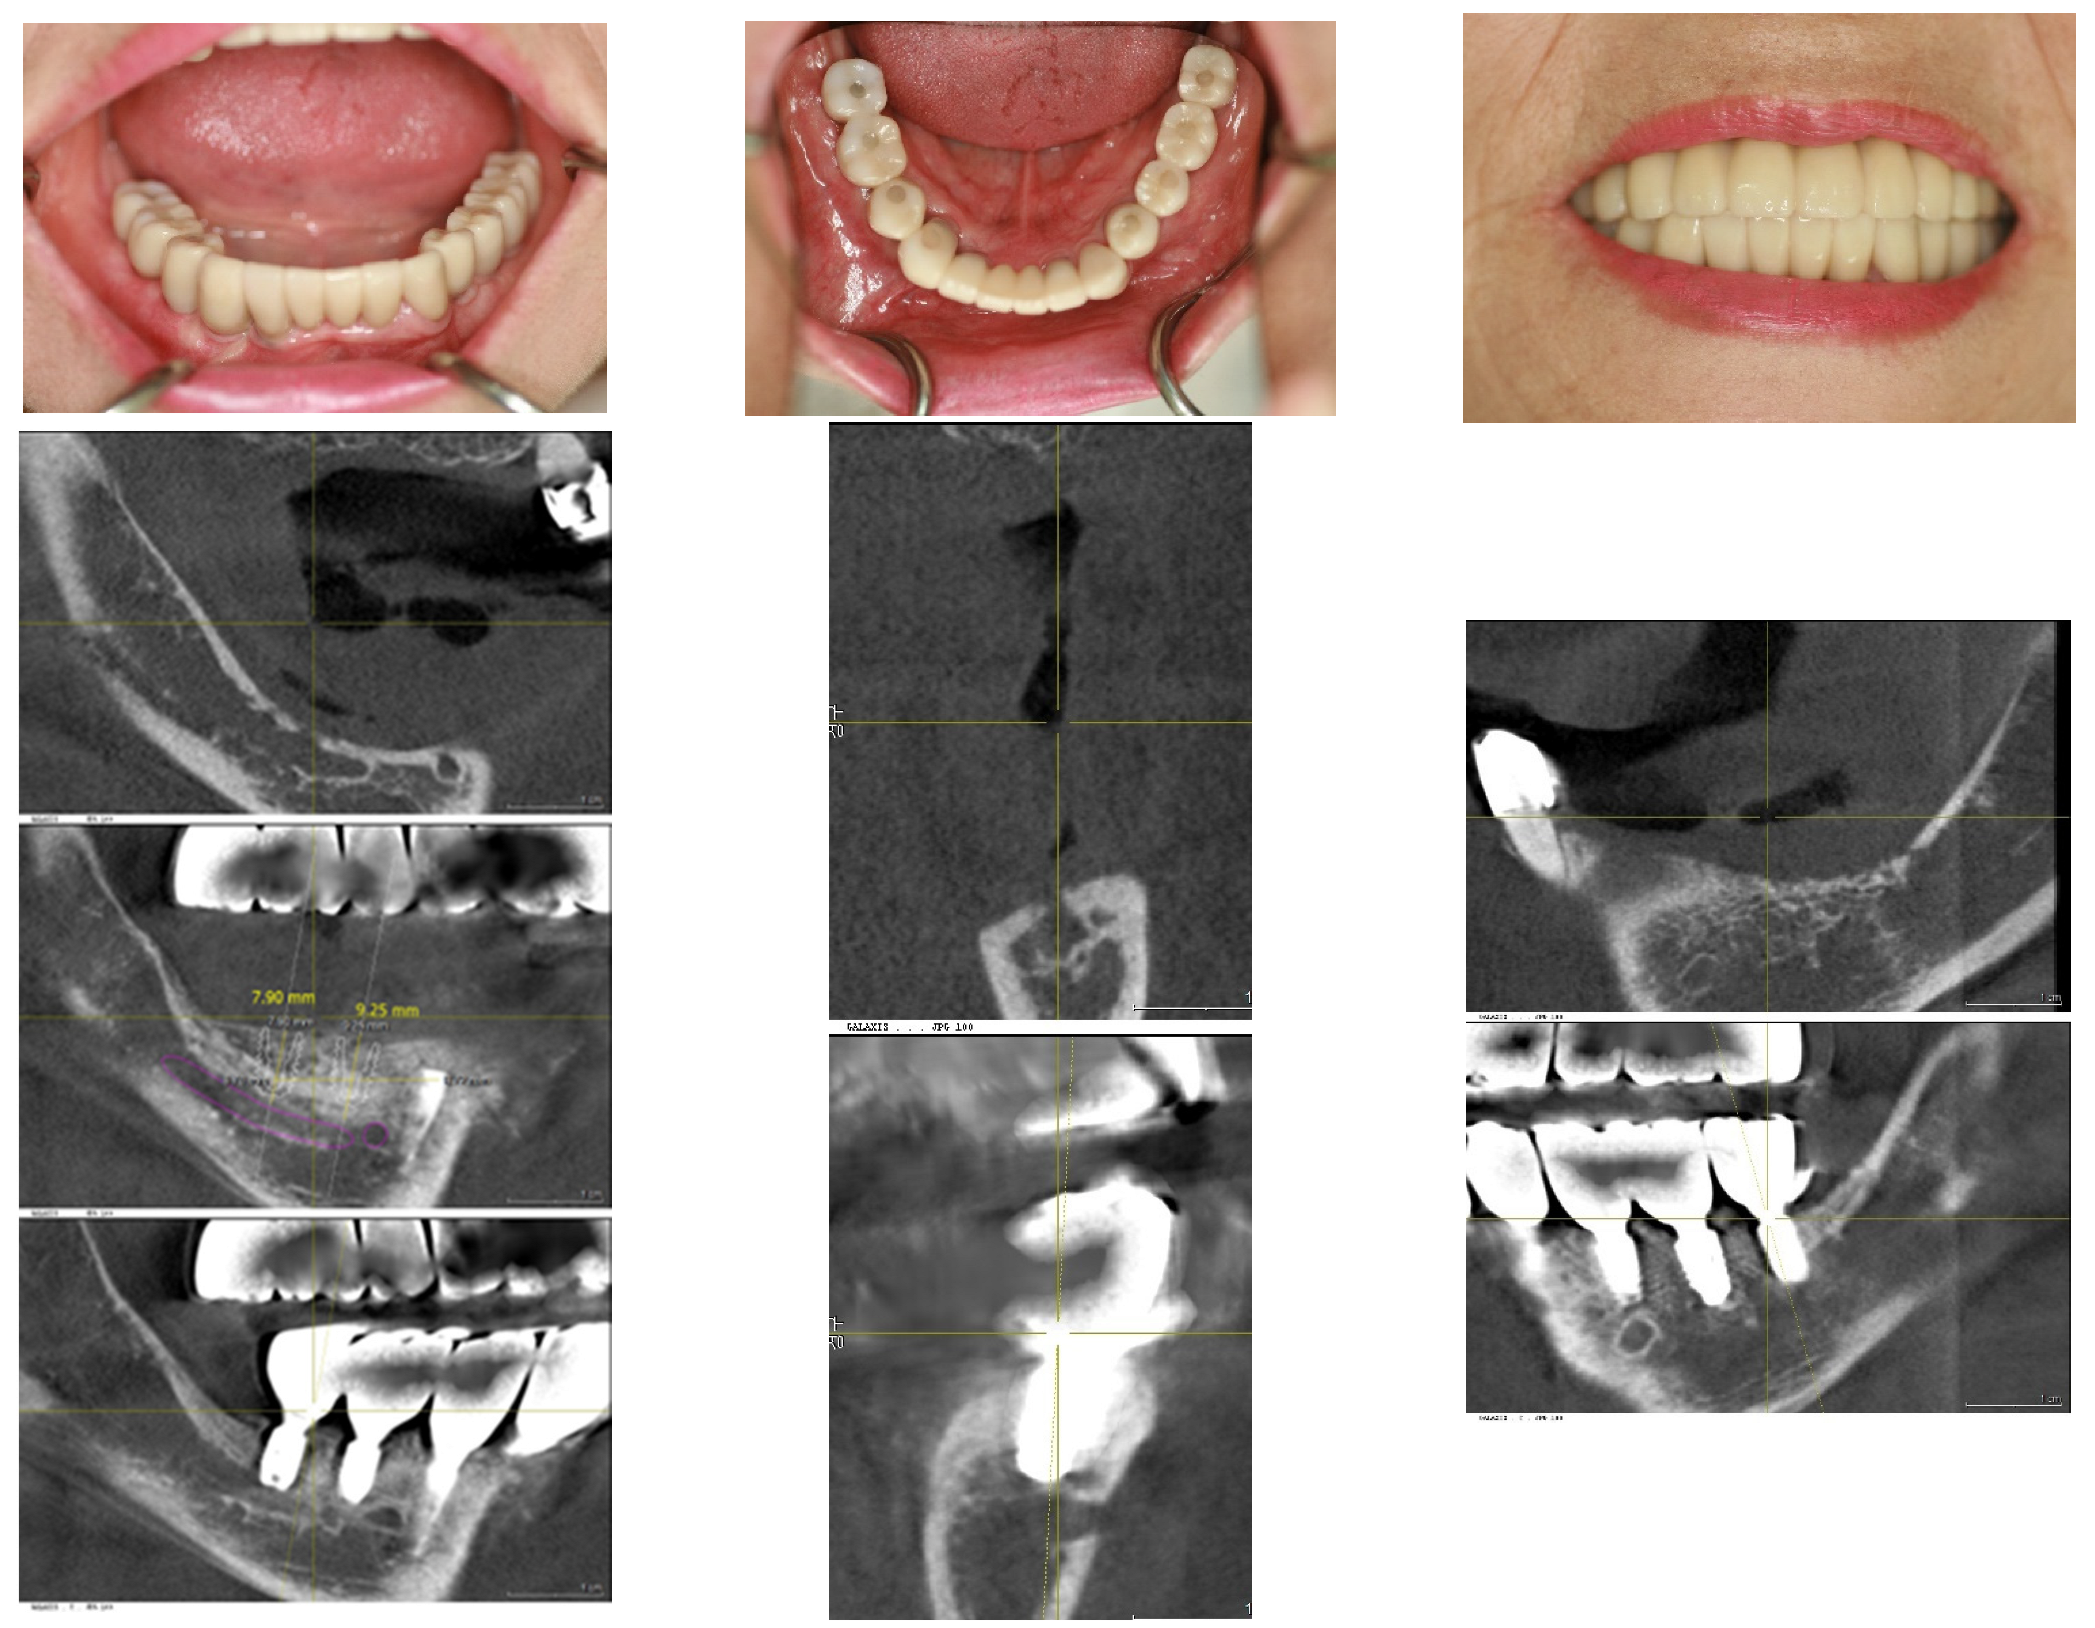

In April 2015, a 65-year-old female patient sought care at Purpose Driven Dental Clinic, reporting discomfort with her old upper and lower removable dentures. She had no medical history other than controlled hypertension, which was managed with medication. She had her lower posterior teeth extracted decades ago and had undergone several replacements of her removable dentures before visiting my clinic. Examination revealed severely atrophic upper and lower edentulous ridges, save for three remaining teeth (right upper canine, right upper incisor, and left lower canine). Panoramic X-ray imaging indicated that the residual crestal bone height in the first molar area above the upper border of the inferior mandibular canal was 2.2 mm on the right side and 4.0 mm on the left side. The patient expressed her desire for replacing the edentulous areas with fixed prostheses using dental implants (Figure 1).

Figure 1. The initial intraoral photos showed that the upper arch had only two teeth remaining, both with root caries and periapical abscesses, while the other teeth were missing. The lower arch displayed severely atrophic mandibular edentulous ridges, with only the left canine remaining. Please note that the residual crest of the right edentulous ridge is flush with the level of the mouth floor.